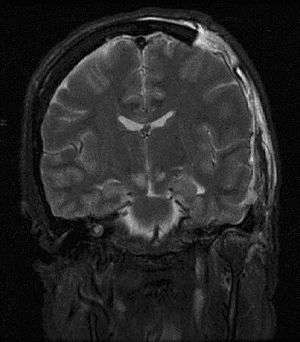

Severely raised ICP, if caused by a unilateral space-occupying lesion (e.g. a hematoma) can result in midline shift, a dangerous sequela in which the brain moves toward one side as the result of massive swelling in a cerebral hemisphere. Midline shift can compress the ventricles and lead to hydrocephalus.[12] Prognosis is much worse in patients with midline shift than in those without it. Another dire consequence of increased ICP combined with a space-occupying process is brain herniation (usually uncal or tonsilar). In uncal herniation, the uncus hippocampus becomes compressed against the free edge of the tentorium cerebelli, frequently leading to brainstem compression. If brainstem compression is involved, it may lead to respiratory depression and is potentially fatal. This herniation is often referred to as "coning".